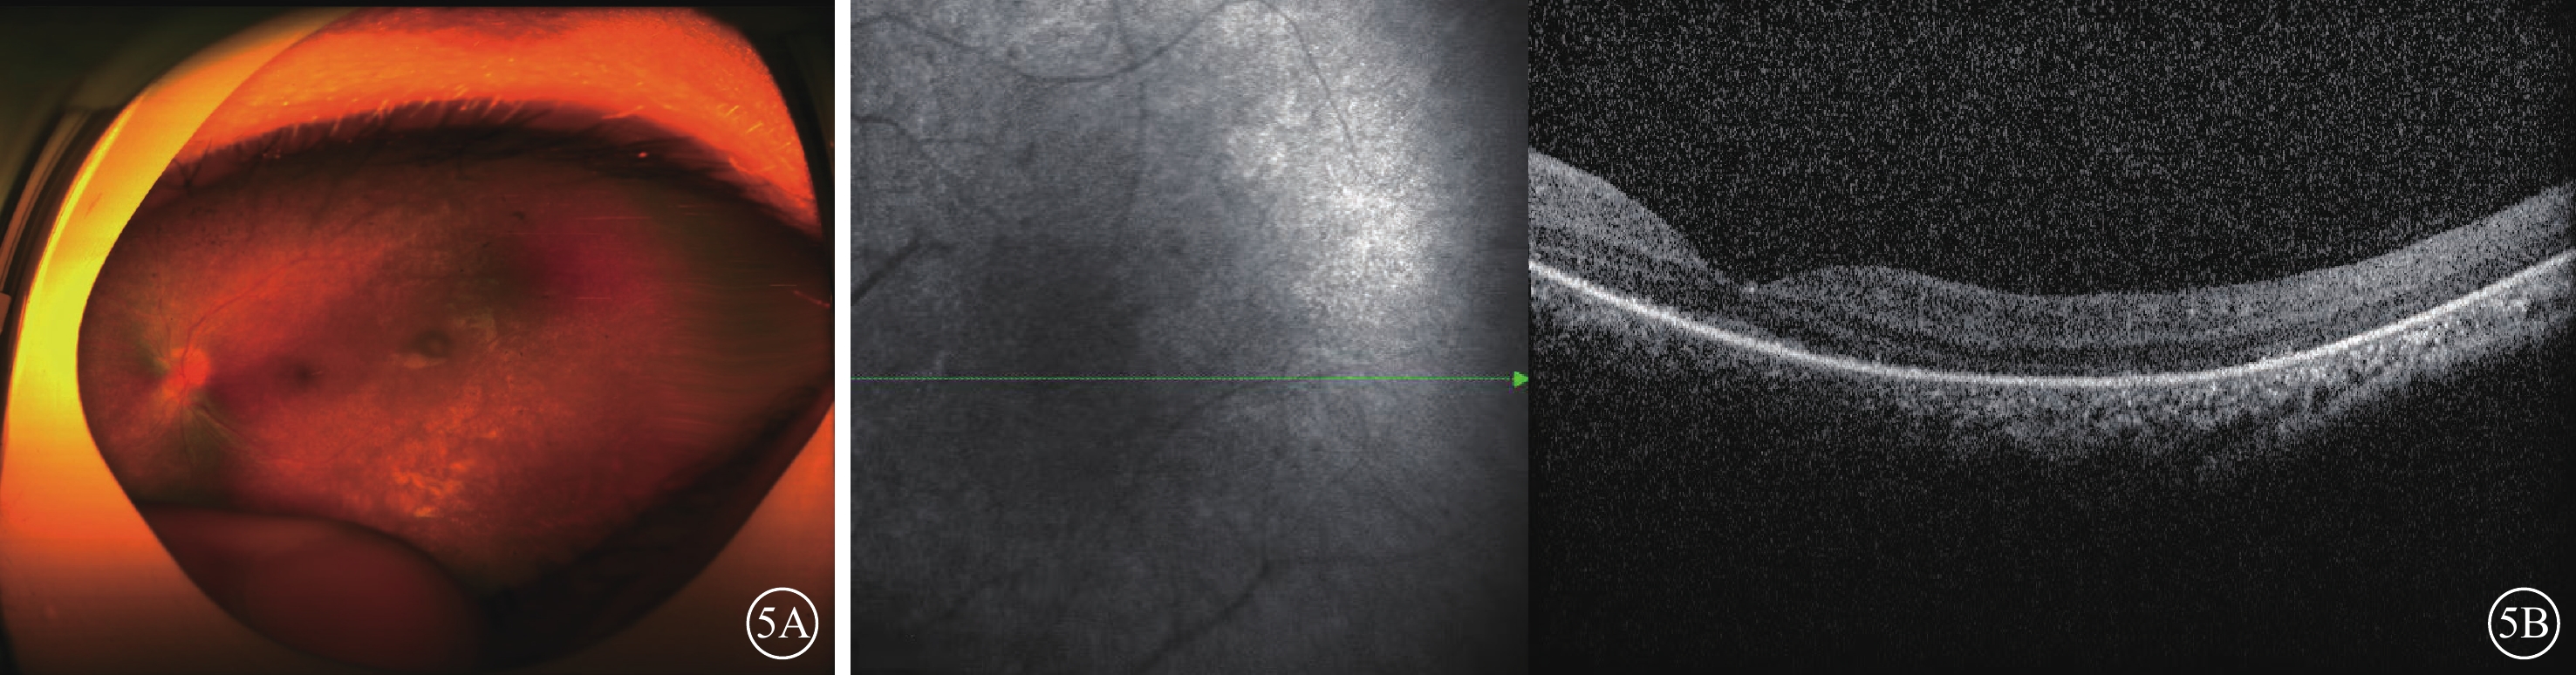

家系2先證者(Ⅱ2),女,12歲。雙眼自幼畏光伴視力低下。否認夜盲等癥狀。心臟彩色多普勒超聲檢查,提示心內大體結構及左心功能未見明顯異常;聽力檢查,提示雙耳高頻聽力損傷下降,存在感音神經性耳聾。眼科檢查,BCVA:右眼數指/1 m(+9.50 DS/-1.00 DC×75°),左眼手動/40 cm(+10.50 DS/-1.50 DC×180°)。雙眼紅、綠色均不能辨認。不能固視,明顯水平眼球震顫。雙眼眼前節未見明顯異常。雙眼視網膜平伏,大量色素沉著,黃斑中心凹反光不清(圖5A)。OCT檢查,雙眼視網膜前膜,神經視網膜外層結構紊亂并變薄,累及黃斑中心凹,視網膜色素上皮粗糙;右眼同時可見神經視網膜點狀中強反射信號,局部脈絡膜反射信號增強,伴光衰減(圖5B)。ff-ERG檢查,雙眼視錐視桿細胞嚴重受損(圖6A~6E)。先證者父親(Ⅰ1)、母親(Ⅰ2)、兄長(Ⅱ1)眼部及全身檢查均未見明顯異常。